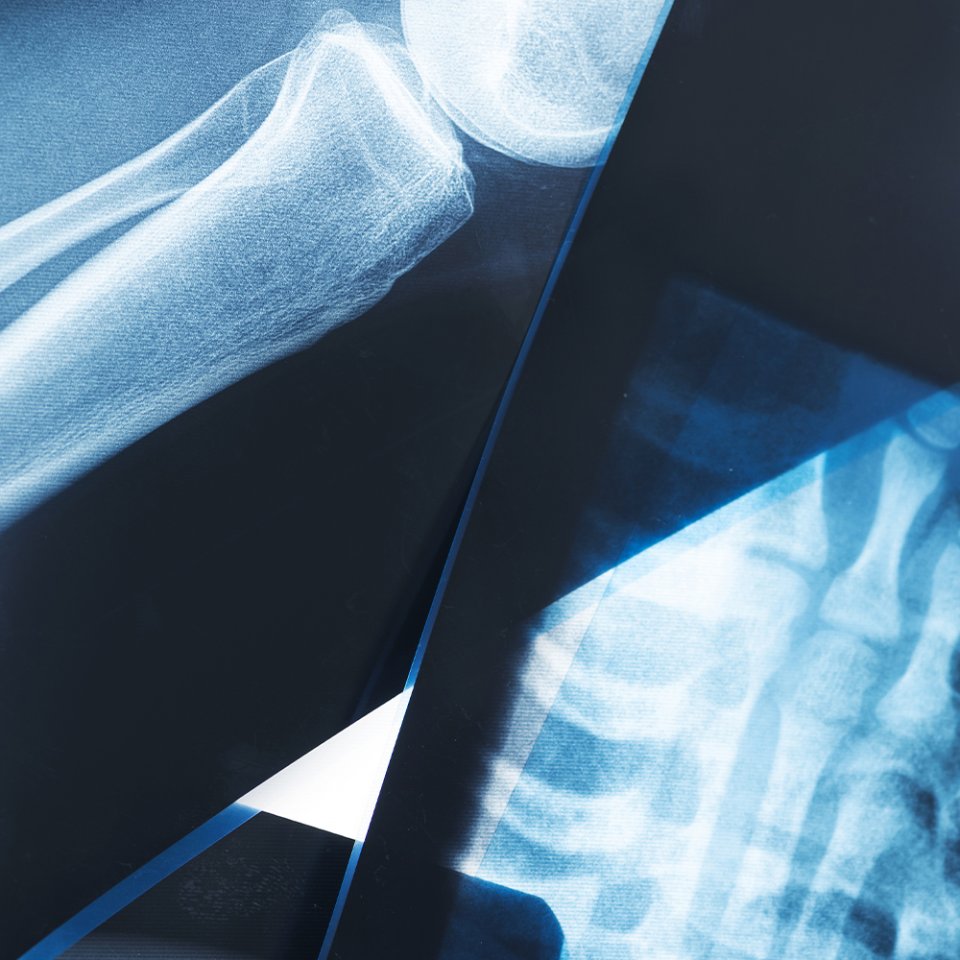

What is Trauma & Fracture Surgery?

Trauma and fracture surgery focuses on the treatment of broken bones, dislocations, and complex injuries caused by accidents, falls, or sports-related trauma. These procedures aim to restore bone alignment, ensure proper healing, and help patients return to daily activities as quickly and safely as possible.

How is Trauma & Fracture Surgery Performed?

Procedure: Alignment of bone fragments followed by fixation (plates, screws, rods, or nails).